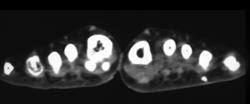

Multiple Pelvic Fractures